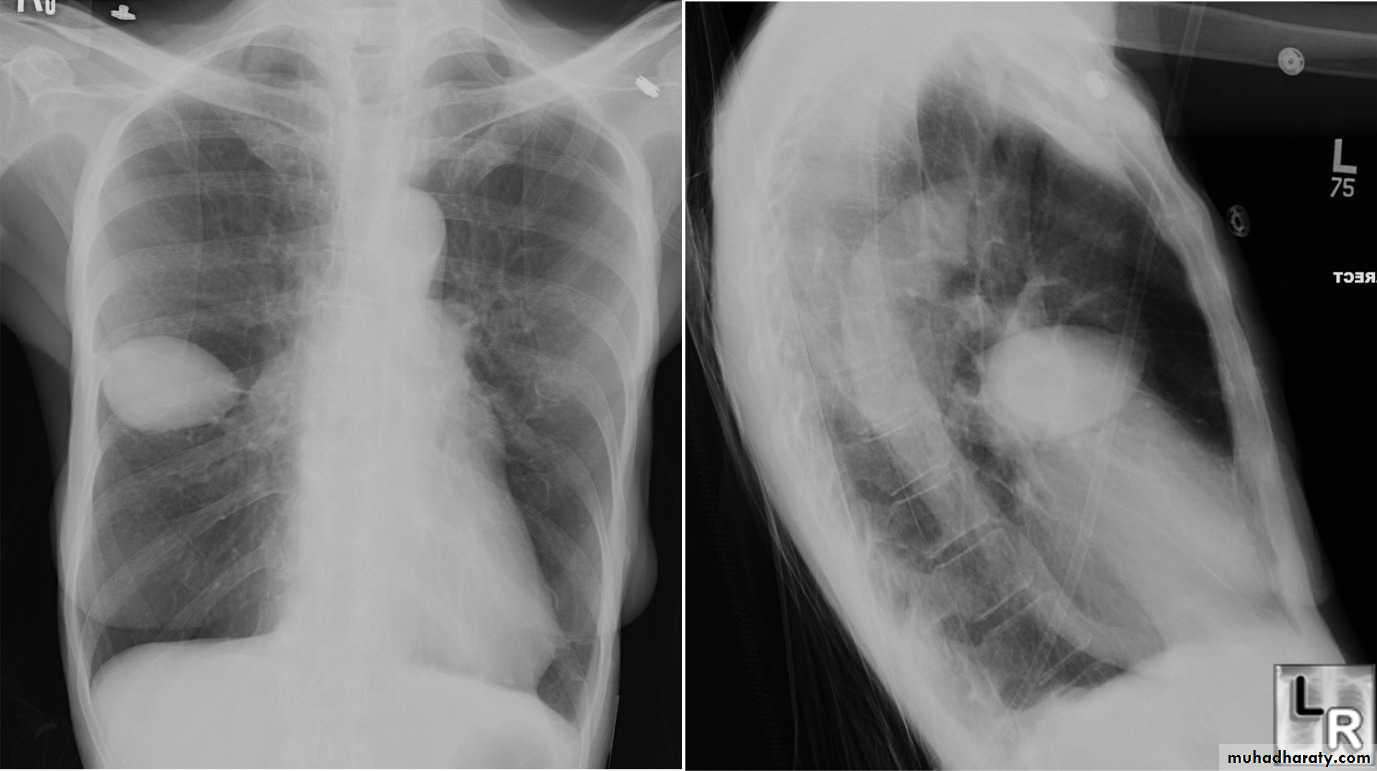

Standard views are the PA & Lateral

PA ( frontal ) VIEW LT. LATERAL VIEW

Other views: AP, oblique, Decubitus, apical, inspiratory, expiratory.

Lateral view

IndicationsAnterior mediastinal mass

Encysted pleural fluids

Posterior basal consolidation